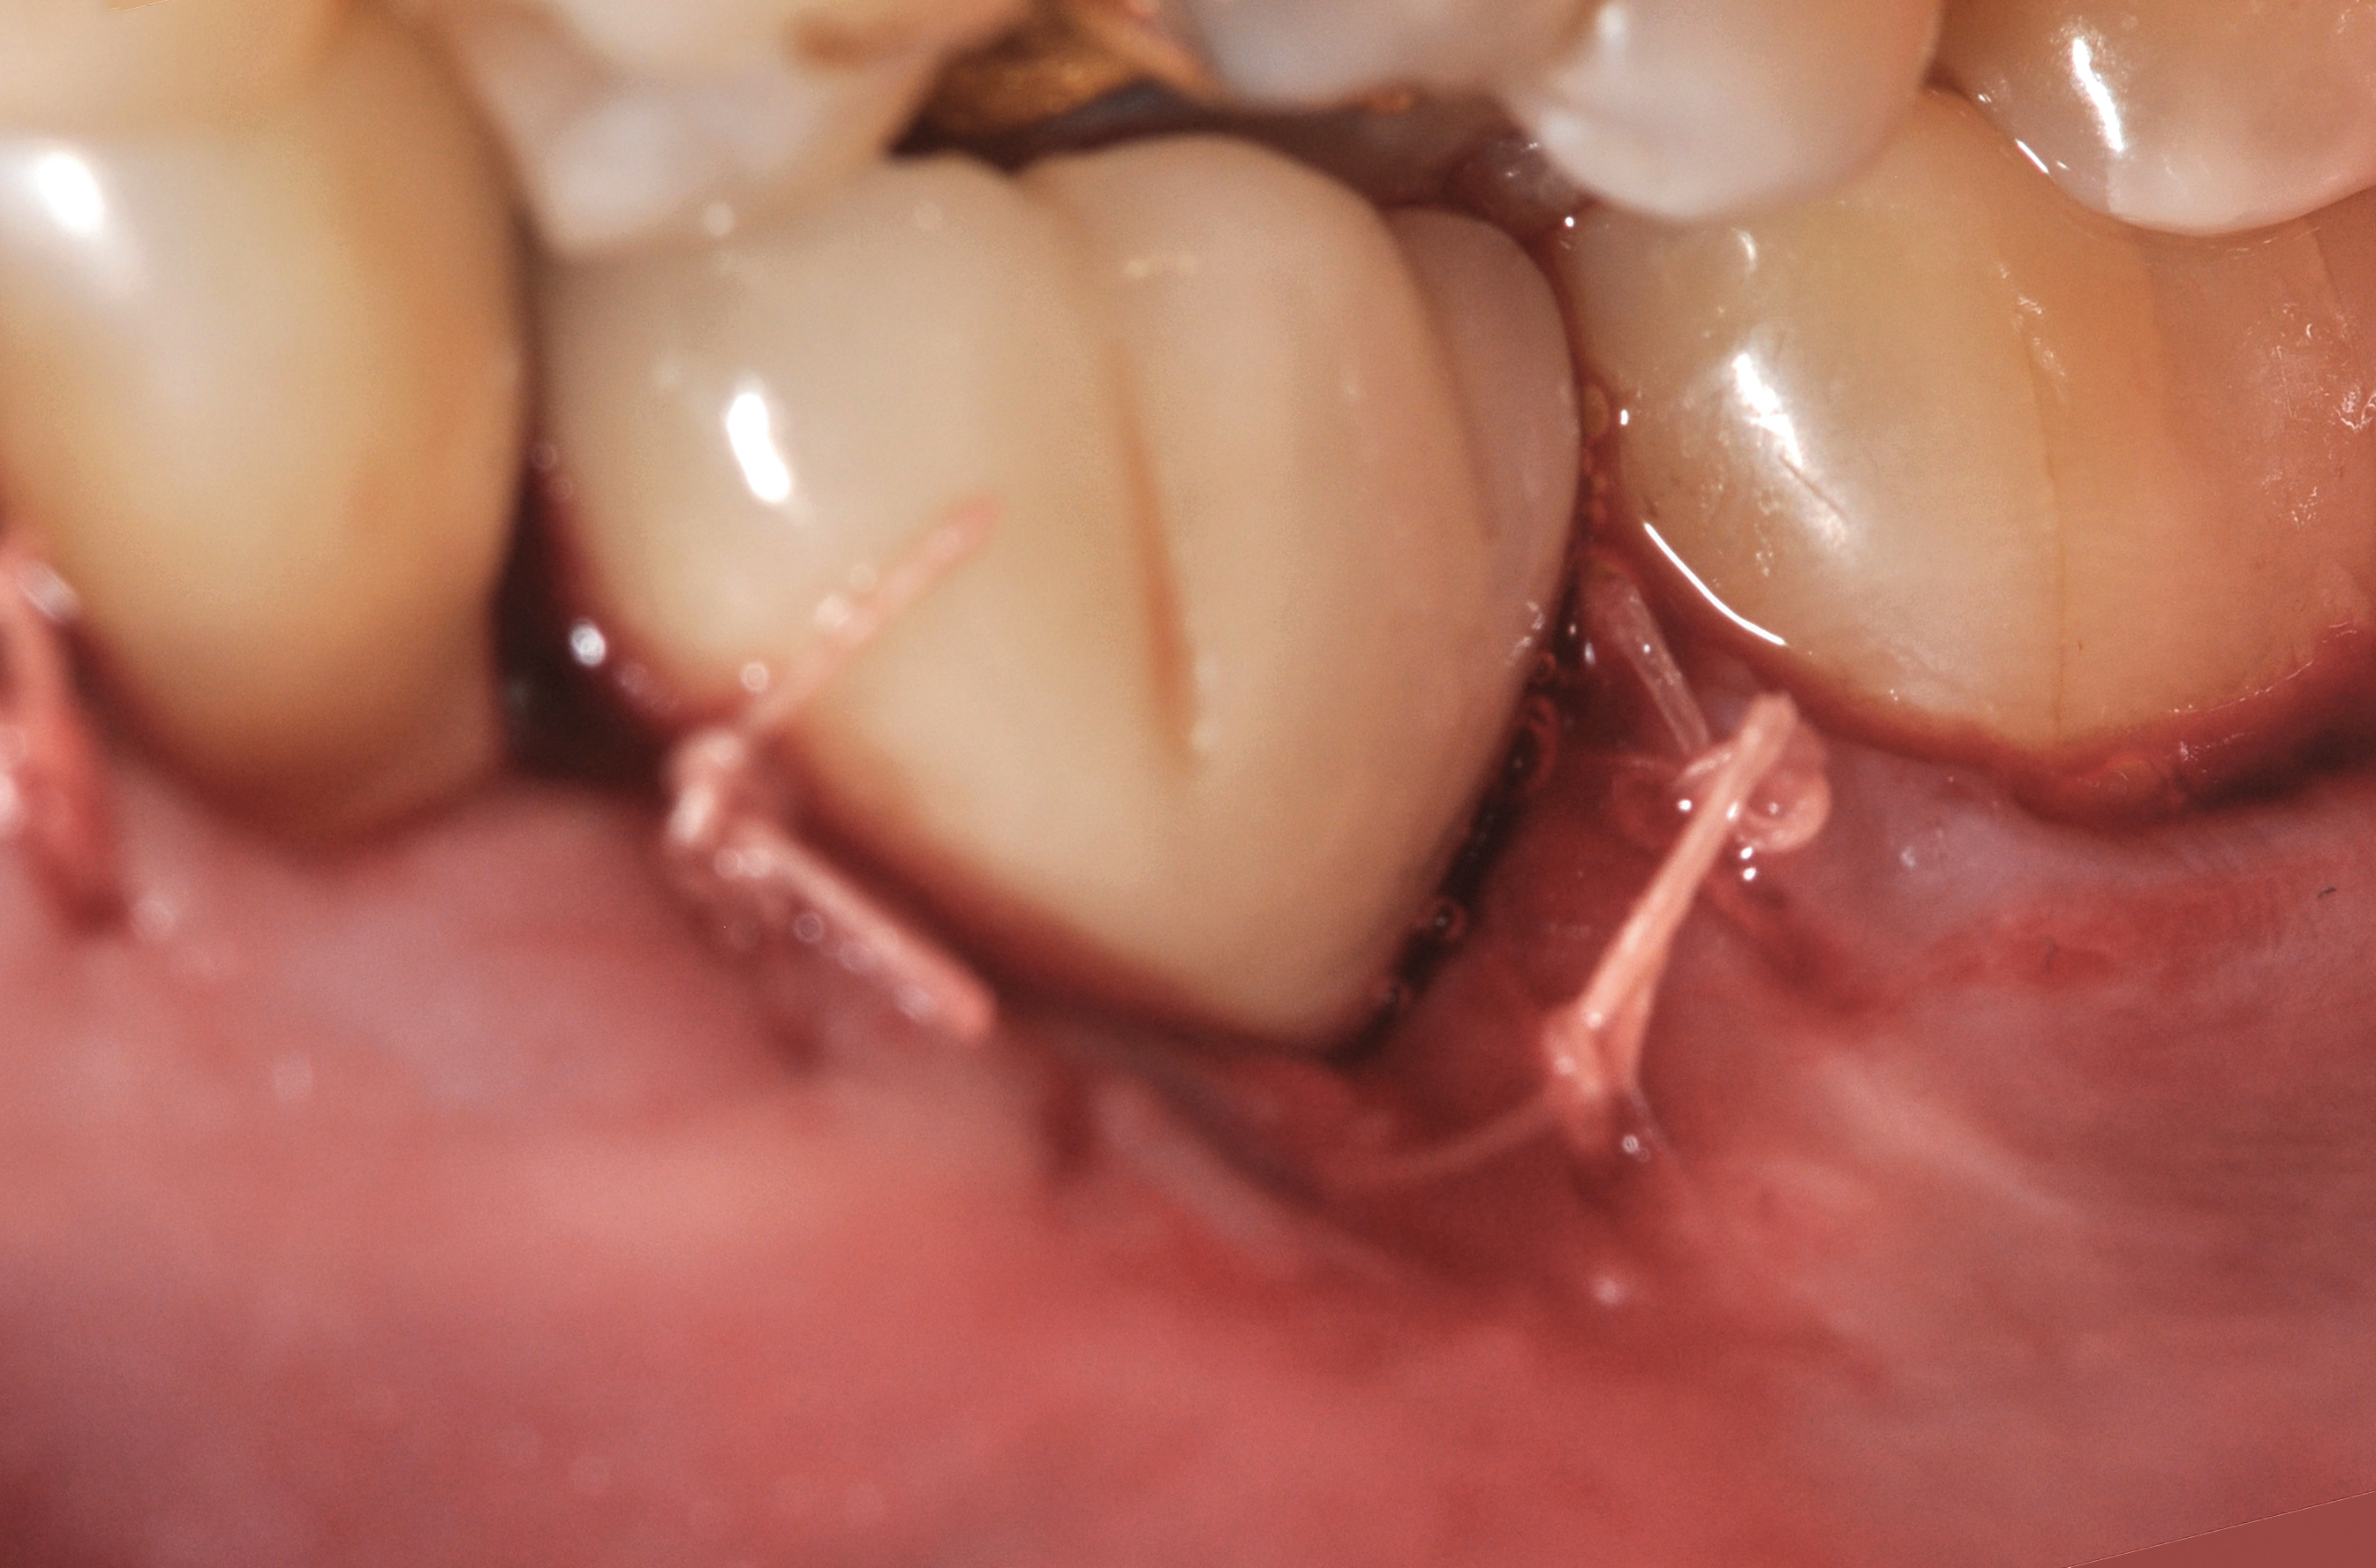

The crown and screw-retained custom abutment were removed, and a surgical cover screw was placed into the implant, thereby allowing spontaneous gingival augmentation in situ (Figure 33 and Figure 34). Note that the lingual aspect of the implant site was significantly more coronal than the labial aspect, which was positive because the defect would be limited to a facial–lingual defect. A fixed RBR bridge was cemented on the adjacent teeth and used as a tooth-supported transitional provisional restoration (Figure 35). A few weeks were allotted to let the soft tissue heal and migrate around the cover screw (Figure 36) to see if there would be complete coverage, thereby allowing a soft-tissue augmentation procedure to be performed with primary flap closure as in clinical scenario No. 2. The major obstacle in achieving a positive tissue response was that the implant depth was also deficient because the implant–abutment connection was at the level of the free gingival margin. It was decided that the best treatment option would be to remove the implant. A high-powered reverse-torque device (Fixture Remover Kit, NeoBiotech, www.neobiotechus.com) was used to remove the implant atraumatically (Figure 38 through Figure 41). The implant socket was allowed to heal for several months not unlike an extracted tooth (Figure 42). A new implant was placed in a better position from both a restorative and esthetic perspective (Figure 43), and after a few months of healing, a new crown was made (Figure 44). A satisfactory functional and esthetic result was achieved (Figure 45 and Figure 46) without employing pink porcelain.

Fig 36. Two weeks after RBR placement, the soft tissue did not adequately cover the implant. The problem was in poor implant angulation and proper depth to allow the soft tissues to cover over.

Fig 38. A reverse-torque screw was placed into the implant.

Fig 39. A counter-torque device was placed over the reverse-torque screw.

Fig 40. The implant was easily unscrewed within minutes in a minimally invasive manner with less trauma to the surgical site.